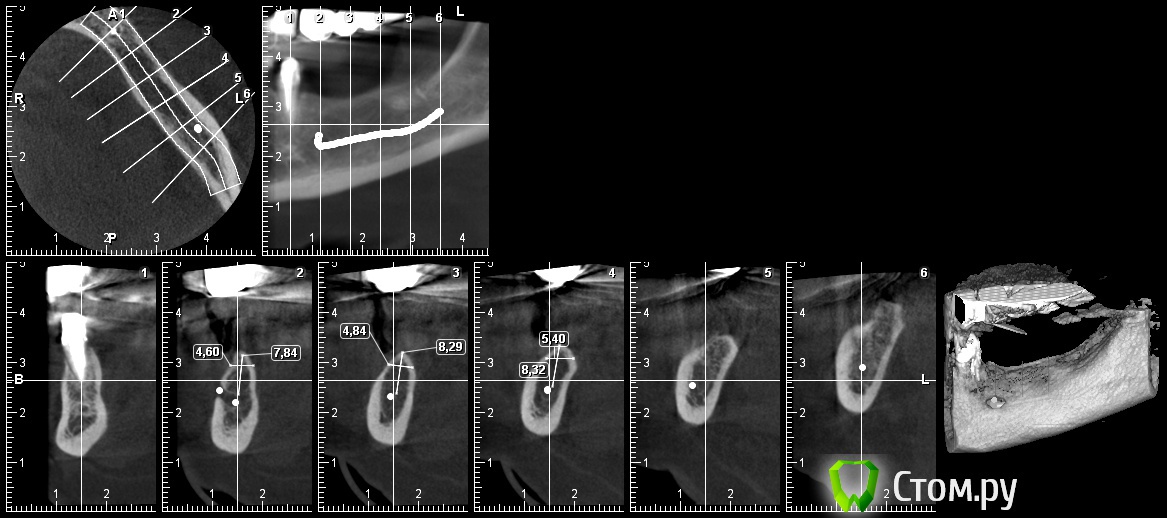

DoktorDre Опубликовано 16 января, 2014 Поделиться Опубликовано 16 января, 2014 (изменено) Судя по снимку, тут стоило бы рассмотреть расщепление или "обычную" имплантацию с одномоментной костной пластикой и мембранойЩепануть можно но мало вертикально- до антогонистов не меньше 10мм. 8 ки можно поставить, но это компромиссная работа - как и по эстетике , как и по прикрепленной десне, с сомнительным прогнозом долгосрочным. Здесь 3 дэ по кюри подходит.Или может " крыша коробки")) но последнее, наверное. Изменено 16 января, 2014 пользователем DoktorDre 2 Ссылка на комментарий

Dc.Petrov Опубликовано 16 января, 2014 Автор Поделиться Опубликовано 16 января, 2014 (изменено) я считаю,для медиального импланта ширины не хватит, как ,впрочем, и высоты Изменено 16 января, 2014 пользователем Dc.Petrov Ссылка на комментарий